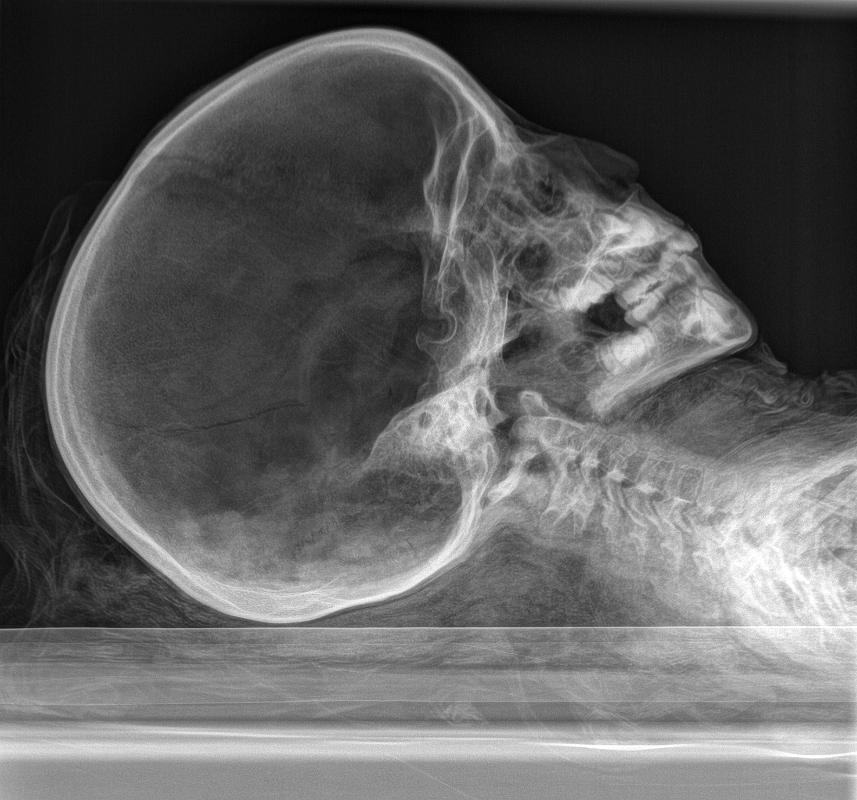

mummy, boy, human remains

- The mummy of a small boy.